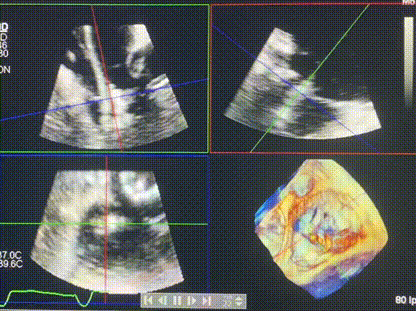

術(shù)后超聲顯示僅殘余微量瓣周漏

LuX-Valve Plus經(jīng)血管三尖瓣置換系統(tǒng)此次“出海”圓滿完成,術(shù)后Rodrigo Estévez-Loureiro教授對LuX-Valve Plus經(jīng)血管三尖瓣置換系統(tǒng)的器械性能和治療效果大為稱贊,認為LuX-Valve Plus的手術(shù)體驗非常好。術(shù)后即刻超聲顯示三尖瓣反流幾乎完全消失,血流動力學改善顯著,患者恢復快。在面對復雜解剖結(jié)構(gòu)、超聲影像質(zhì)量不佳、有起搏導線干擾時,Lux-Valve Plus也體現(xiàn)了極強的適應(yīng)性。Thomas Modine教授和Anson Cheung教授也肯定了LuX-Valve Plus術(shù)中操作的便捷性,認為LuX-Valve Plus容錯率高,對術(shù)中影像的依賴較小,后期希望可以更多的應(yīng)用LuX-Valve Plus三尖瓣置換系統(tǒng)于臨床實踐,讓更多的三尖瓣重度反流患者盡早獲益,改善預后。